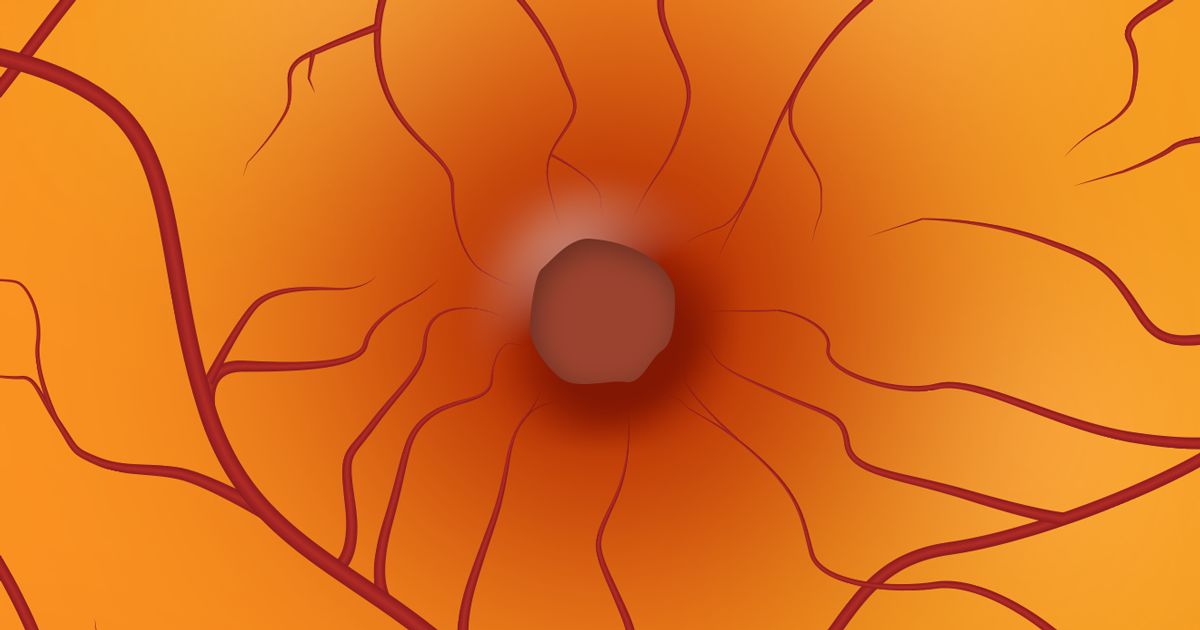

Makula deliği nedir?

Makula deliklerinin ne olduğunu ve nasıl oluştuklarını anlamak için, ilk önce göz anatomisi hakkında biraz bilgi edinmek önemlidir.

Makula (veya makula lutea) retinanın merkezinde çok küçük bir noktadır. Görsel olarak, retinanın en hassas parçasıdır. Makula, görme keskinliğinden, ayrıntılı santral görmeden (örneğin okuma, sürüş ve yüzleri tanıma) ve renkli görmeden sorumludur.

Makula deliği, bulanık ve bozulmuş santral görmeye neden olan ve tipik olarak aniden oluşan makulada küçük bir kırıktır.